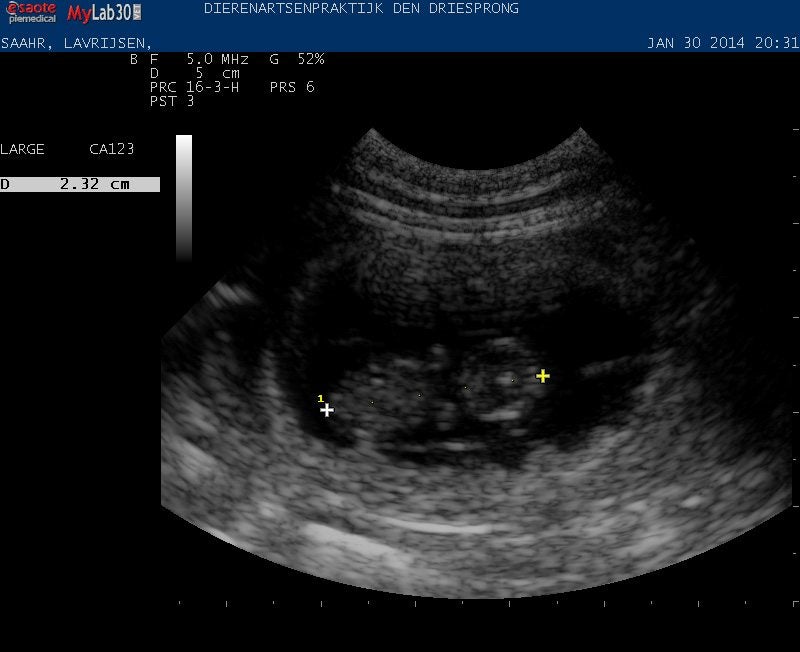

Echo

2013-01-30 bij Dierenartsenpraktijk den Driesprong, Reusel

Yeahhh... Saahr is drachtig!!